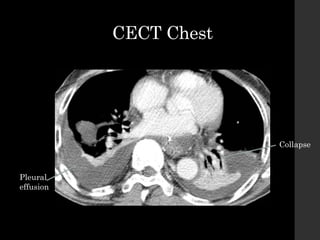

CECT Chest

Collapse

Pleural

effusion